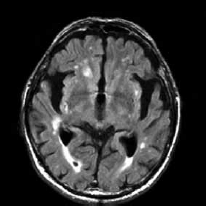

Paciente de 72 anos é referida ao consultório neurológico com queixas progressivas de perda de memória, alterações no comportamento e dificuldade em realizar tarefas diárias complexas, observadas pela família nos últimos dois anos. A avaliação cognitiva estruturada revela déficits significativos na memória episódica, funções executivas e orientação visuoespacial. O exame neurológico é notável por marcha apráxica e presença leve de rigidez axial. A ressonância magnética (RM) encontra-se a seguir.

(https://www.google.com/url?sa=i&url=https%3A%2F%2Fradiopaedia.org)

Com base nesses achados clínicos e radiológicos, das seguintes condições, assinale a que representa, corretamente, o diagnóstico mais provável.